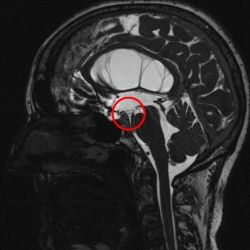

Präoperative MRT Untersuchung.

Präoperative MRT Untersuchung. Der rote Kreis zeigt den Boden des 3. Ventrikels, welcher im Rahmen einer endoskopischen VZS eröffnet wird.